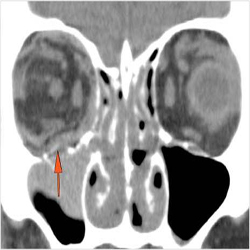

Proptosis is present.

The optic nerve has a stretched appearance.

The posterior aspect of the globe is tented.

There are signs of a decompressed globe.

There is evident general optic sheath swelling or swelling at the junction of the globe and sheath to suggest an optic sheath hematoma.